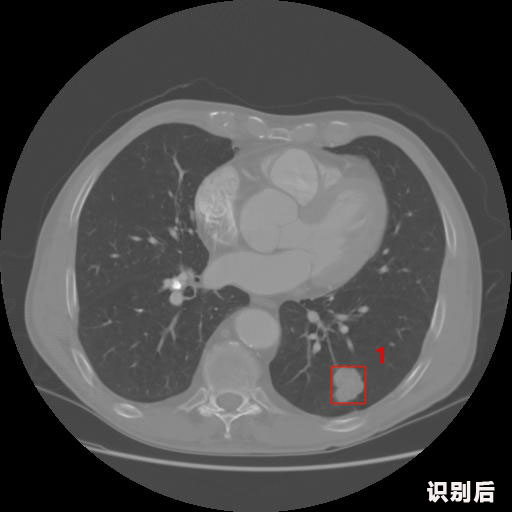

1.發(fā)現(xiàn)肺結(jié)節(jié)的可能性為95.56%---位于框指數(shù)位置:[331.70554 366.13406 365.21707 403.96234]